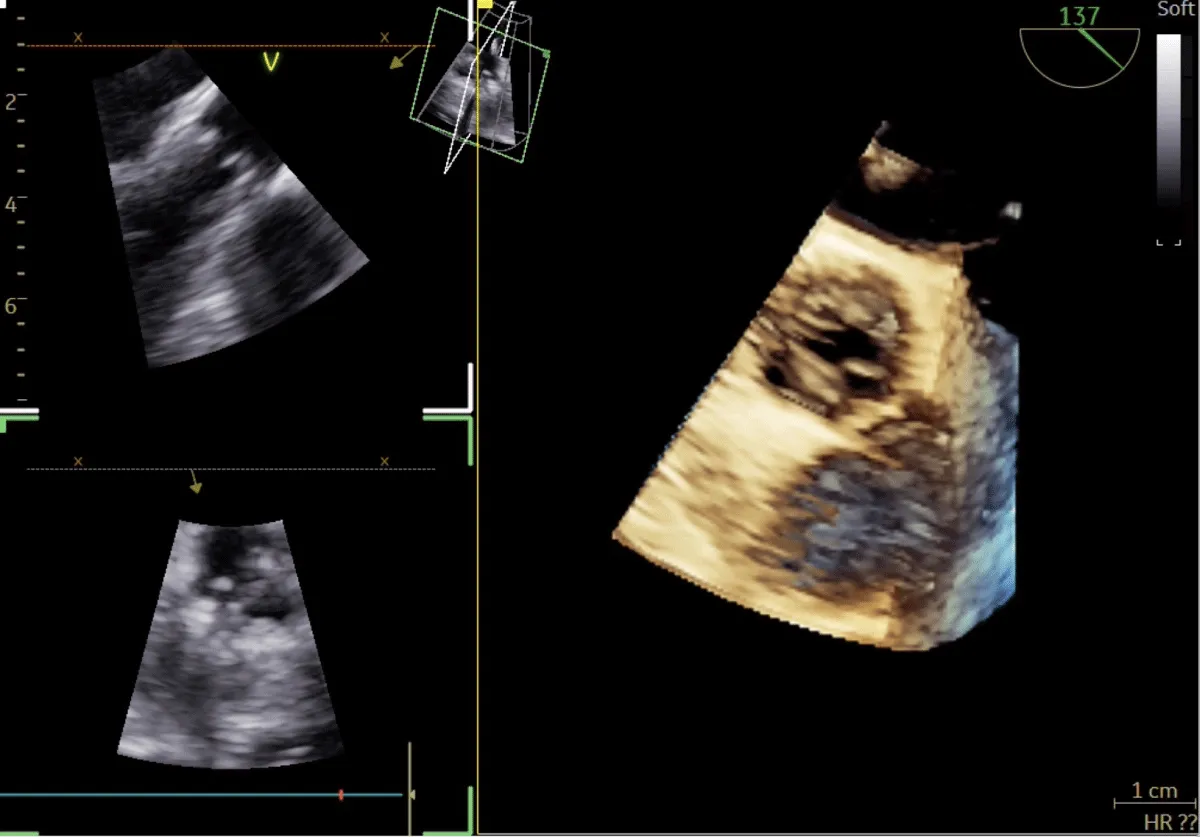

Following a single dilatation, the AV gradient decreased from 82 mm Hg to 30 mm Hg without aortic regurgitation (AR). Subsequently, the mitral valve (MV) was dilated with a 26 mm Inoue balloon (Figures 4,5) (Video 2). After a single dilatation, the MV gradient was reduced from 35/21 mm Hg to 12/5 mm Hg, and the MV area increased from 0.5 cm2 to 1.6 cm2 (Figure 6)

Figure 5: 4Dimensional multiplanar transoesophageal echocardiography – Balloon dilatation of the mitral valve with Inoue balloon.

Download Image

Figure 6: 4Dimensional multiplanar transoesophageal echocardiography – mitral valve after balloon dilatation.